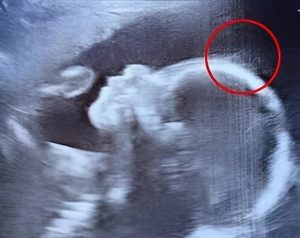

« Attendez… est-ce que je vois bien… des cheveux ? », lance-t-il, un sourire dans la voix. Intrigué, un confrère le rejoint pour observer l’écran, et la conversation dérive sur le futur style rock’n’roll du petit être. Sur le moniteur, de fins filaments se balancent au gré du liquide amniotique, créant un tableau à la fois rare et émouvant.

Une chevelure fœtale d’une clarté exceptionnelle

L’équipe soignante se veut immédiatement rassurante : avoir des cheveux in utero est un processus parfaitement naturel. Ce qui est inhabituel, en revanche, c’est leur abondance et la précision avec laquelle ils sont captés par l’appareil. Une telle visibilité à ce stade de développement est plutôt rare.